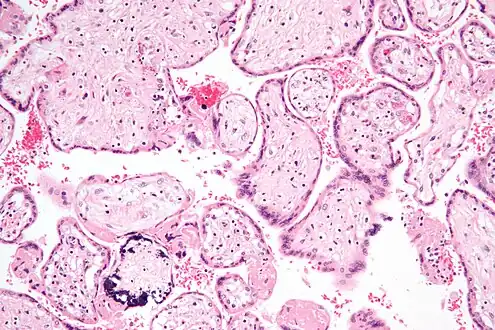

Micrograph of cytomegalovirus (CMV) infection of the placenta (CMV placentitis), a vertically transmitted infection: The characteristic large nucleus of a CMV-infected cell is seen off-centre at the bottom right of the image, H&E stain.

Apart from infecting the fetus, transplacental pathogens may cause placentitis (inflammation of the placenta) and/or chorioamnionitis (inflammation of the fetal membranes).